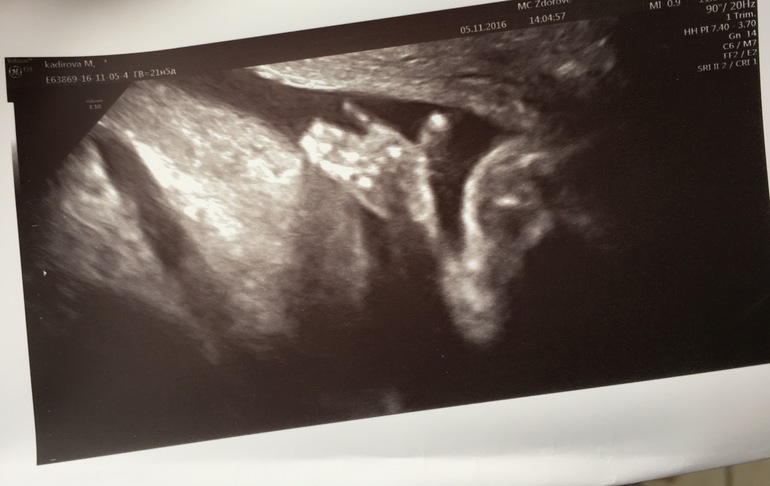

Второй скрининг пройден !)

УЗИ, КТГ, доплерВсе у нас хорошо , сроку соответсвует. Вес 413 грамм. Сегодня 21.6 недель . Все отлично , только пуповина 2 сосуда. Но врач говорит что все нормально. Мужичок мой показал себя во всей красе😄Пристала узистка к нашему маленькому носу . 5 мм. К сыну первому тоже я помню она прикопалась из-за маленького носа , и ниче , родился с аккуратненьким носом )

Я даже мужу показала ваш снимок узи!!! Круто!!! Прям достоинство во всей красе😂👍👍👍💕поздравляю вас с пройденным вотрым скринингом! нам это еще предстоит...

Вот это точно мужик,с большой буквы М. Очень круто. Поздравляю вас и в дальнейшем только благополучной беременности